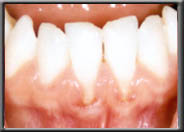

Some people are born without sufficient attached gingiva to prevent the muscle in the alveolar mucosa from pulling the gum down. In these cases the gum slowly continues to recede over time, even though the patient may be very conscientious with their oral health. This is not an infection, as is seen with periodontal disease, but rather simply an anatomic condition. Unfortunately, bone recession is occurring at the same time the gum is receding. This is because the bone, which is just under the gum, will not allow itself to become exposed to the oral cavity and moves down with the gum.

With the wear and tear of time, even normal attached gum can be worn away, generally from vigorous brushing. This often happens in people with naturally thin tissues, or when the tissues have been stretched during orthodontics. If there is still adequate attached gum to act as a barrier to the muscle, the treatment for recession is to ensure further damage isn't done when brushing. However, if the attached gum is worn to the point where it cannot resist the constant pull of the mucosa, recession will continue unless a new hard band of gum is placed. Unchecked, the recession can cause tooth loss as the bone recedes with the tissue and tooth support weakens.